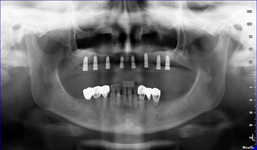

Pomocí tohoto přístroje je možné zjisti skutečnou situaci v čelistních kostech pacienta tedy množství kosti - můžeme změřit skutečnou šířku i výšku kosti, i kvalitu kosti (hustotu) v místě uvažované implantace. 3D (tříprostorové) zobrazení umožňuje

zvýšit prostorovou představu operatéra ještě před vlastní operací a zároveň pacientovi lépe objasnit a ukázat oblast plánovaného zavedení implantátu.

Pacient „neumí číst“ RTG snímky, ale díky 3D zobrazení vidí „svoji skutečnou čelist“ – např. jak je nízká či úzká, vidí průběh nervu nebo velikost čelistní dutiny, což mu umožní i pochopení nutnosti v některých případech provést pomocné zákroky

ještě před vlastním zavedením implantátu (více - Augmentace - kostní štěp, sinus lift, kostní granulát...).

Lékař si vytvoří všechny typy zobrazení potřebných pro naplánování – tedy 2D snímky (panoramatický), příčné řezy i 3D model.

Vidí zde i důležité anatomické útvary – čelistní dutinu, průběh nervu atd. Po proměření množství kosti – šířky i výšky vybere z databáze vhodný typ implantátu a umístí ho do požadované lokality.

Ihned vidí jeho pozici ve všech 3 rovinách a na všech snímcích i 3D modelu. Může upravovat podle potřeby jeho pozici, sklon atd.